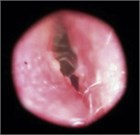

In acute otitis externa (AOE), the patient complains of ear pain, which is always uncomfortable and sometimes unbearable, often accompanied by drainage and a blocked sensation, decreased hearing, and sometimes by fever. Close follow-up and reevaluation for the possible need for antibiotics drops are necessary.

acute otitis externa

AOE